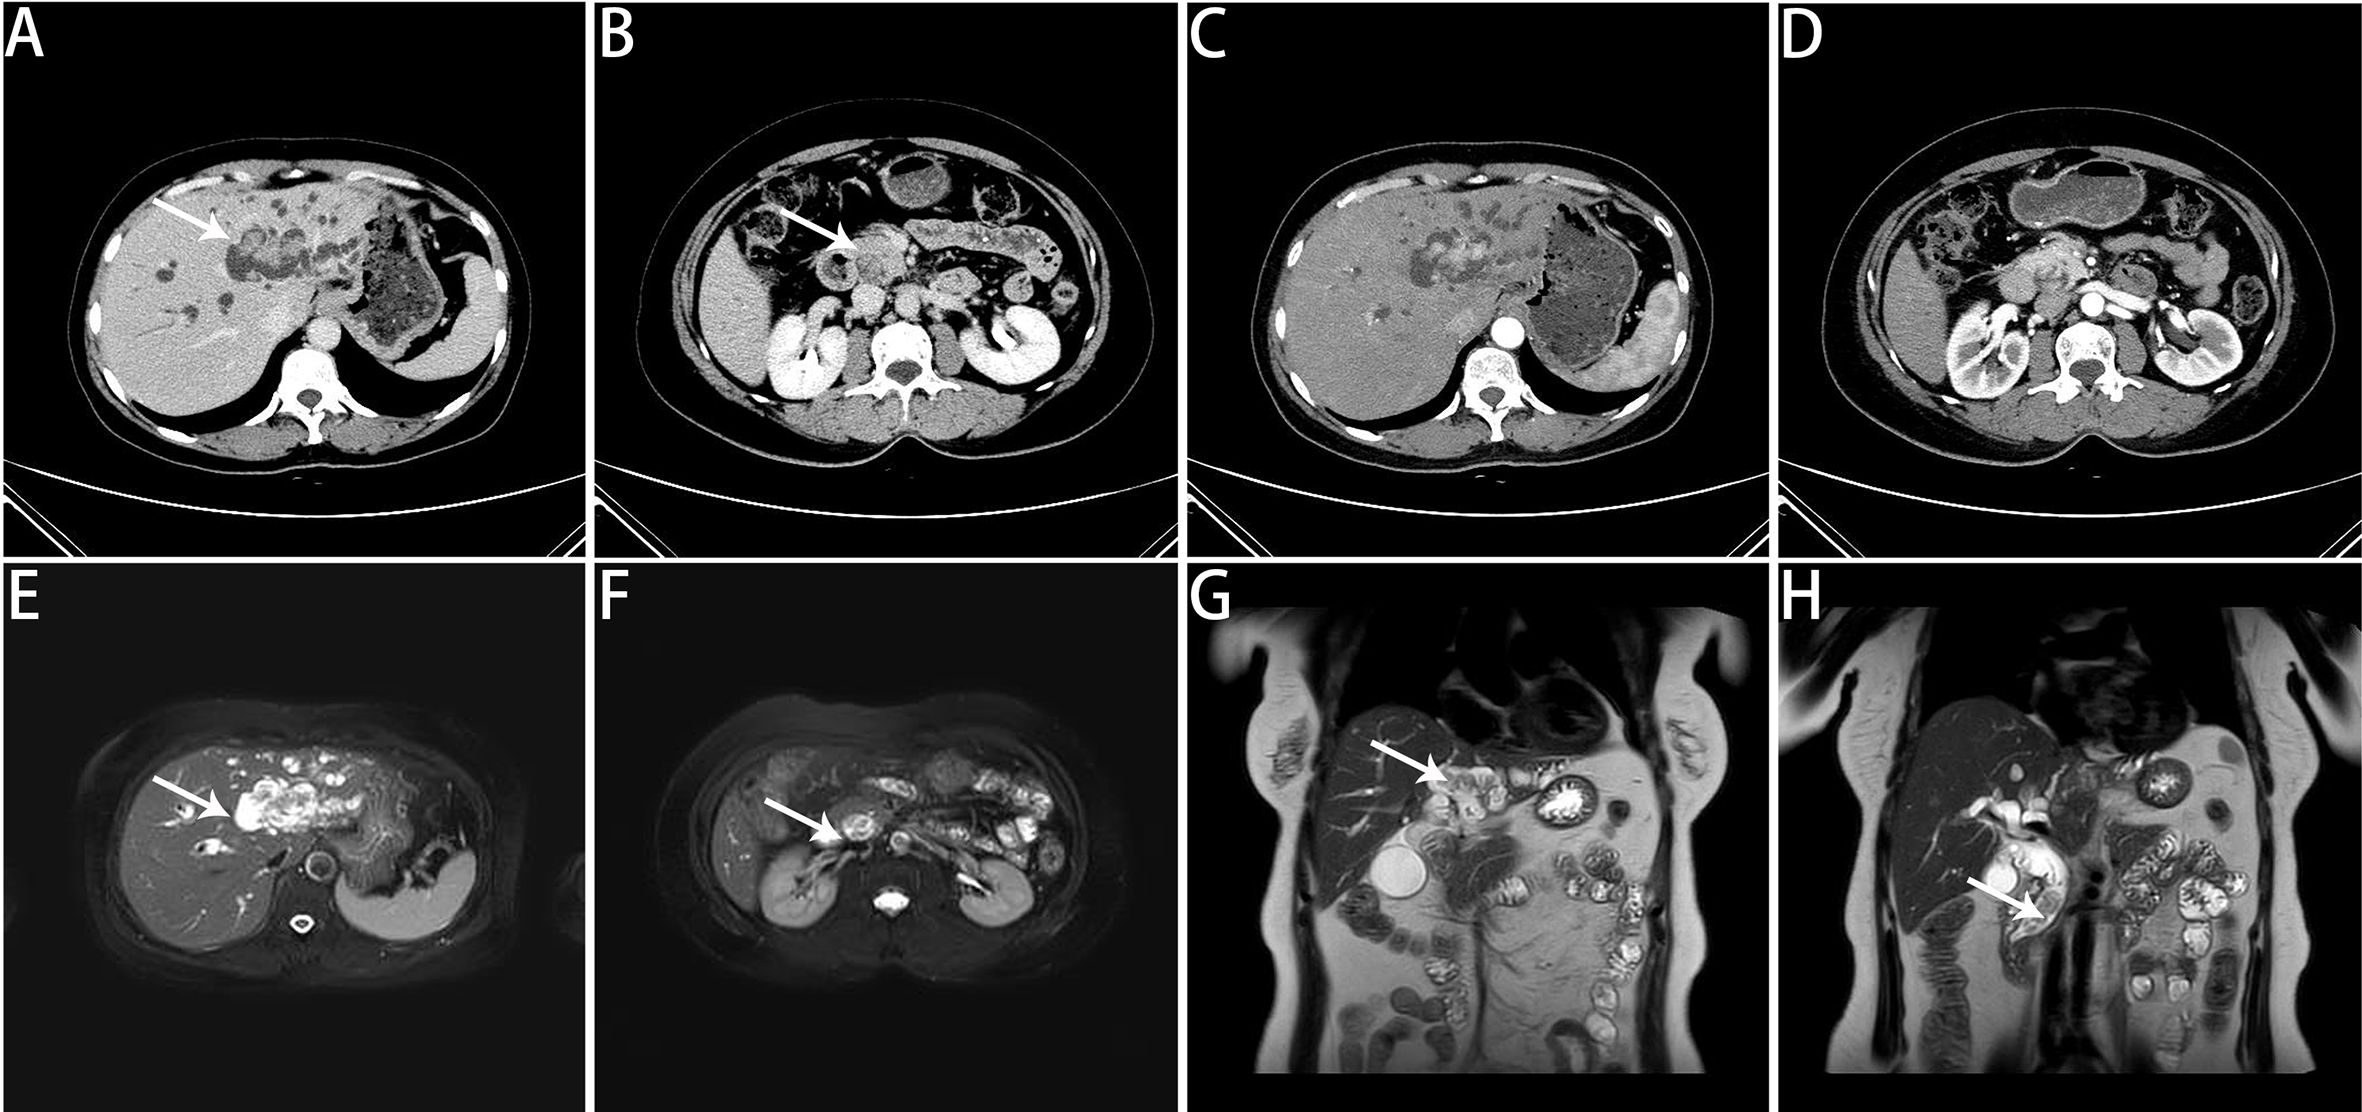

Background: Laparoscopic hepatopancreatoduodenectomy (LHPD) is a while very complex procedure for biliary malignancies combined with intrahepatic bile duct invasion, but there are few reports of related surgeries due to high postoperative complications and mortality. In this study, we report a case of tubular adenoma with high-grade intraepithelial neoplasia of the homologous left hepatic bile duct combined with the common bile duct. Case presentation: A 53-year-old female was admitted to the hospital with jaundice for one week. Imaging studies showed space-occupying lesions in both the left intrahepatic and common bile duct. We performed LHPD, and the patient was discharged on postoperative day 13 without bile and pancreatic fistula. Pathology confirmed tubular adenoma with high-grade intraepithelial neoplasia in both sites. Conclusion: LHPD can be an option for radical surgery in carefully screened patients with biliary malignancies with intrahepatic invasion.